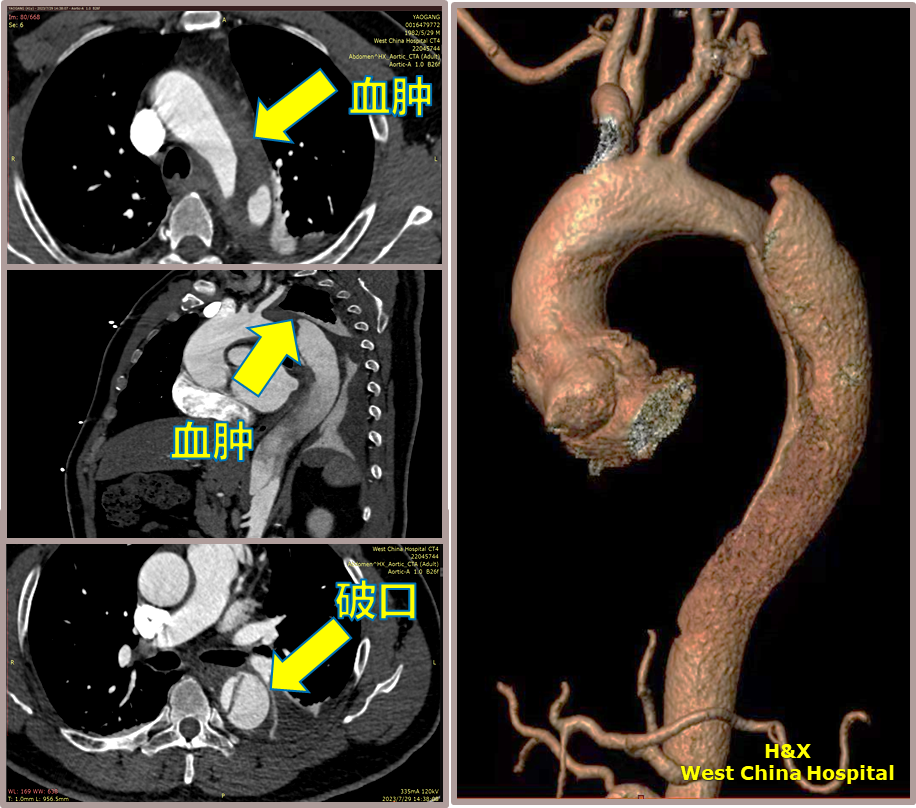

男性,42岁,胸痛3天;

既往史:高血压,规律服用降压药物;

手术史:10年前外院行主动脉腔内修复+左颈总及左锁骨下烟囱支架植入;

夹层动脉瘤CTA:逆撕A型主动脉夹层,升主动脉及无名动脉见夹层累及,左颈总及左锁骨下动脉烟囱支架。

术前影像